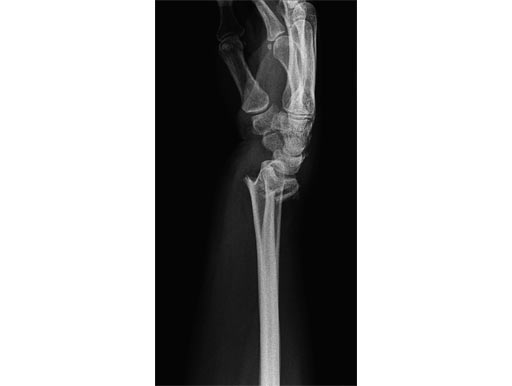

54-year-old female with 23-C3 fracture after fall

External fixator due to severe soft-tissue trauma. Palmar plate 1 week later. .